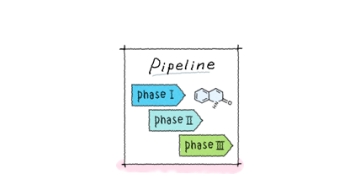

Otsuka Pharmaceutical is dedicated to the research & development of highly-innovative drugs and diagnostics. Leveraging our research culture of curiosity, determination and unconventional thinking, we strive for solutions that only Otsuka can deliver, to improve the health of people across the world.

Our R&D philosophy places emphasis on encouraging individual researchers to take the untraveled path, pursuing fresh ideas within a collaborative, accommodating environment. Supported by the global integration of our research and development institutes in Asia, the U.S. and Europe, the result has been epoch-making drugs.

Otsuka Pharmaceutical's first drug discovery research institute opened in 1971. By choosing to tackle unaddressed medical needs, we put ourselves on the path to creating new therapeutic approaches and unprecedented drugs. We prioritize our efforts on psychiatric diseases, neurologic diseases and oncology. Other research and development is in cardio-renal and nephrology, gastrointestinal, infectious diseases, ophthalmology and dermatology.